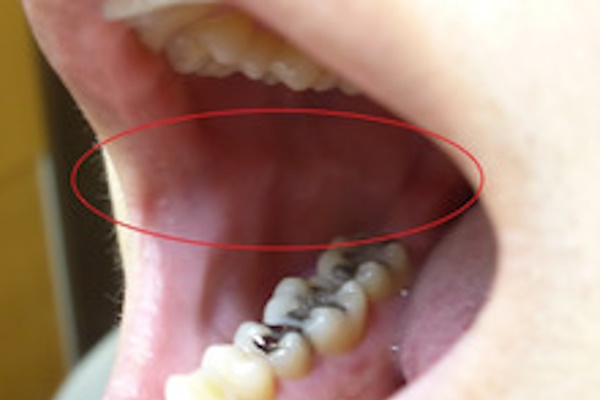

頬や舌の圧痕

また、同じように舌の両脇にも歯痕と呼ばれる歯型の痕が付きます。

圧痕自体は特に害のあるものではなく、食いしばりが解消されれば自然と消えてなくなります。